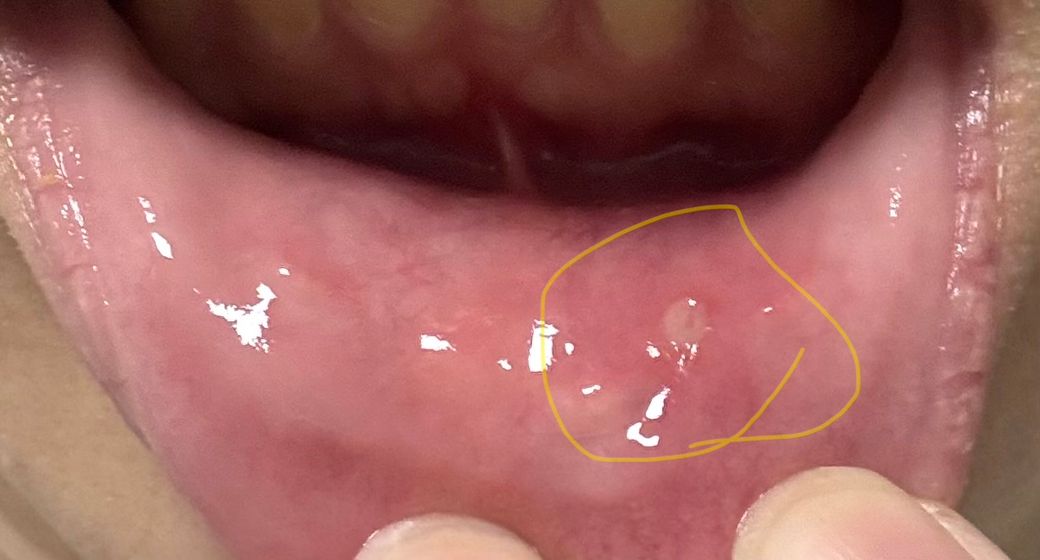

어제부터 났고 가만히 있어도 아파요ㅠㅠ 색은 살짝 하얗고 동그란게 났는데 이빨에 찍혀서 생긴 상처인지 아님 뭐가 난건지 모르겠어요

• 1번 째 사진

이빨에 의해서 입술 점막이 떨어져 나가도 이렇게 되고, 아프타성 궤양에서도 이렇게 생길 수 있습니다.

• 사진과 경과를 종합하면 가장 가능성 높은 것은 아프타성 구내염(일반적인 입병)입니다. 입술 안쪽 점막에 둥글고 하얀 막처럼 보이는 병변, 주변 약간의 발적, 자발통이 있는 양상은 전형적입니다.

병태생리적으로는 점막 미세외상(이로 씹힘), 스트레스, 수면 부족, 영양 상태 변화 등이 유발 요인으로 작용합니다. 단순한 외상성 궤양과 임상적으로 구분이 완전히 명확하지 않은 경우도 많으며, 실제로 외상 이후 아프타 형태로 진행되는 경우도 흔합니다.

임상적 의미는 대부분 양성 경과입니다. 크기가 작고 단일 병변이면 보통 7일에서 14일 사이 자연 치유됩니다.